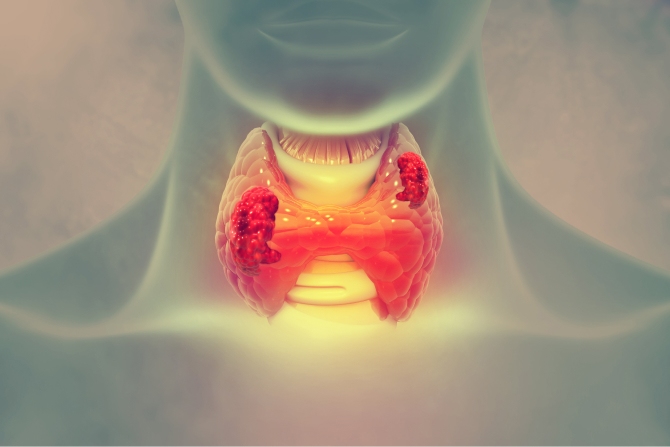

The thyroid gland is an organ located at the front of the neck, just below the larynx or the voice box. It is wrapped around the windpipe, almost like a butterfly with wings spread. Thyroid makes hormones that are responsible for controlling the metabolism of our body. Hypothyroidism (less hormones) and Hyperthyroidism (excess of hormones) are the two main indications of a thyroid disease.

Thyroid conditions like thyroiditis, thyroid nodules, thyroid cancer, compressive thyroid mass, that may or may not require surgery, are best treated by an ENT specialist. Surgery may cause the voice to change and the ENT doctor is trained to manage it because ENT doctors are voice surgeons as well. Thyroid function tests, thyroid scans and ultrasonography are some of the tools that an ENT doctor uses to diagnose the condition and severity of nodules.